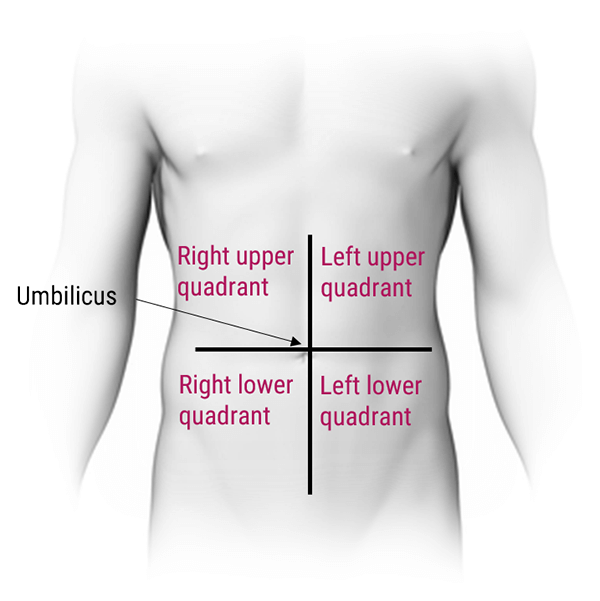

In this section we will explain how the abdominopelvic cavity is divided into 4 quadrants or 9 regions.

As shown in this diagram, the abdominal cavity has been divided into four quadrants: the right upper quadrant, the left upper quadrant, the right lower quadrant, and the left lower quadrant. These quadrants have different abdominal and pelvic organ systems. For example, the right upper quadrant contains the liver, gallbladder, and right colic flexure, whereas the right lower quadrant contains the appendix, terminal ileum, and right ovary in females.

The 4 quadrants are divided by 2 planes: the midsagittal plane and the horizontal plane at the level of the umbilicus.

- The navel also called belly button, the point at which the two planes cross, is the landmark you’ll use to visualize these quadrants while doing assessments

- The terms “left/right” and “upper/lower” are always from the perspective of the anatomical position, not your perspective. Be careful not to mix up your right and left regions, as this is where most students make a mistake!